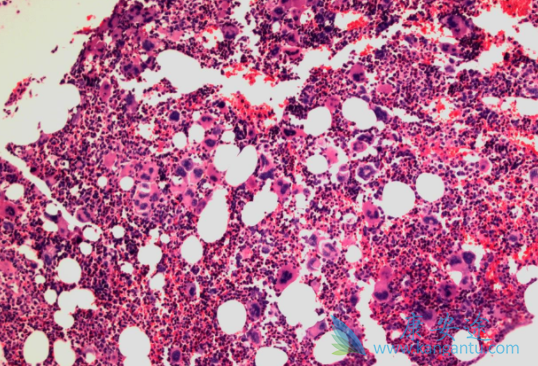

鲁索替尼(jakavi)是诺华研发的治疗骨髓纤维化的靶向药物,主要是与JAK1点为结合。那鲁索替尼既是靶向药物,是不是说明鲁索替尼只针对相应基因突变的骨髓纤维化患者呢?由于鲁索替尼可通过结合JAK1位点,抑制整个JAK-STAT通路,所以,对于所有类型的BCR/ABL经典型骨髓增殖性肿瘤,无论是不是JAK2V617F突变,均能获得良好的疗效。

换句话来说就是,针对JAK12外显子突变,CALR、MPL等突变,甚至所谓三阴性的骨髓增殖性肿瘤,均有疗效。除了骨髓纤维化,鲁索替尼还能治疗其它的骨髓增殖性疾病,比如真红,血小板增多等。虽然鲁索替尼的疗效很好,但是鲁索替尼并不能逆转病情,所以患者在服用鲁索替尼期间,一定要严格遵照医嘱,按剂量科学用药。

鲁索替尼(jakavi)是一种口服JAK1和JAK2酪氨酸激酶抑制剂,最常见血液学不良反应是血小板计数减低和贫血,常见非血液学不良反应是瘀斑, 眩晕和头痛。鲁索替尼可能引发患者血小板技术减低、贫血和中性粒细胞减少,所以患者在治疗期间还要定期监测,如果出现以上情况,可以减少鲁索替尼剂量,或者输血治疗。